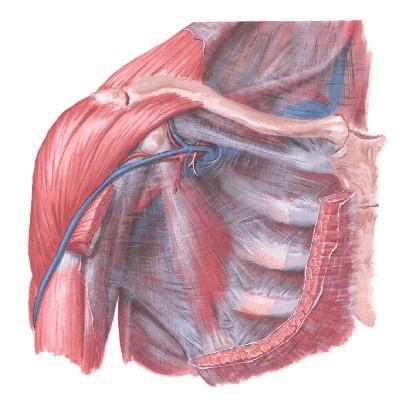

Síndrome de Compresión Neurovascular de la Salida Superior del Tórax.

• Concepto:

Es el conjunto de síntomas y signos en los músculos, hombros y cuello, como consecuencia de una compresión ya sea orgánica o funcional de las vías nerviosas y vasculares arteriales o venosa, que van a inervar e irrigar estos territorios, por las estructuras anatómicas normales o anormales que conforman la zona, desde el cuello hasta el brazo y que son vecinos del paquete neurovascular

Elementos importantes: • 1- Compresión orgánica o funcional. 2- Del paquete neurovascular 3- Por estructuras anatómicas vecinas, normales o anormales. 4- Desde el cuello hasta el brazo.

Etiología: • " Costilla cervical supernumeraria completa o incompleta. " Anomalías de la primera costilla o de la clavícula. " Apófisis transversa larga en C7. " Cayo óseo prominente o fractura desplazada de la clavícula y/o la primera costilla. " Bandas fibrosas congénitas o bandas musculares anómalas. " Variaciones e inserción del músculo Escaleno anterior. " Hipertrofia o contractura espástica del músculo Escaleno anterior. " Anomalias del músculo Subclavio. " Factores congénitos o adquiridos por la posición ocupacional. " Descenso de la cintura escapular. " Estrechamiento de la cintura escapular.

Se reconocen cinco síndromes : 1- Síndrome de la Costilla Cervical Supernumeraria. (Vesalio y Galeno). 2- Síndrome del Escaleno Anterior. (Naffiger 1937 ). 3- Síndrome Costoclavicular. (Falconer y Weddell 1943). 4- Síndrome de Hiperabducción del brazo. (Wright 1945). 5- Síndrome del Pinzamiento Neurovascular.

• Síndrome del Escaleno Anterior: • Por el triángulo Inter.-escalénico pasan el plexo y la arteria subclavia, delimitado por el músculo escaleno anterior por delante, el músculo escaleno medio por detrás y por la primera costilla por abajo, por lo que todo cambio que cause disminución de este espacio, puede traer como consecuencia la aparición de los síntomas. Fig # 3 3. Síndrome Costoclavicular. Ya en este espacio se ven comprometidos los tres elementos del paquete vasculonervioso, apareciendo los síntomas y signos venosos, turgencia venosa, edema del miembro superior, circulación colateral venosa a nivel del hombro. fig # 4 El diagnóstico se realiza con la maniobra costoclavicular I y II.

• A este nivel, los tres elementos del paquete vasculonervioso pasan por detrás del tendón del músculo pectoral menor en su inserción con el proceso coracoideo de la escápula. fig # 1 y 4 El diagnóstico se realiza con la maniobra de hiperabducción del brazo. (foto#7) La sintomatología es similar al del Síndrome Costoclavicular, pero suelen ser menos acentuados los síntomas y signos venosos.